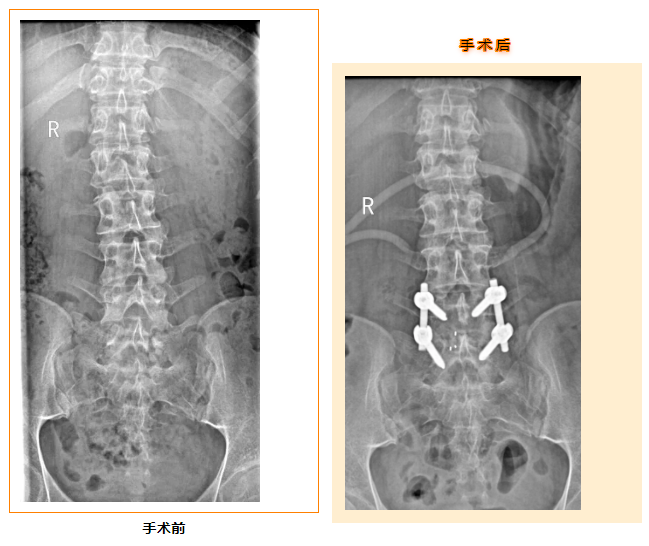

张勇果断与家属耐心沟通,迅速组织术前评估及全院大会诊,在医联体中南大学湘雅三医院骨科苗惊雷教授的精准指导下,9月28日,医院为患者成功开展了腰5骶1节段切开椎板切除椎管及神经根管减压+椎间盘摘除+(Cage)椎间融合+后路钉棒系统内固定术。术后小宇的胀痛症状明显缓解,露出了久违的笑容,家属紧缩的眉头也舒展开来。